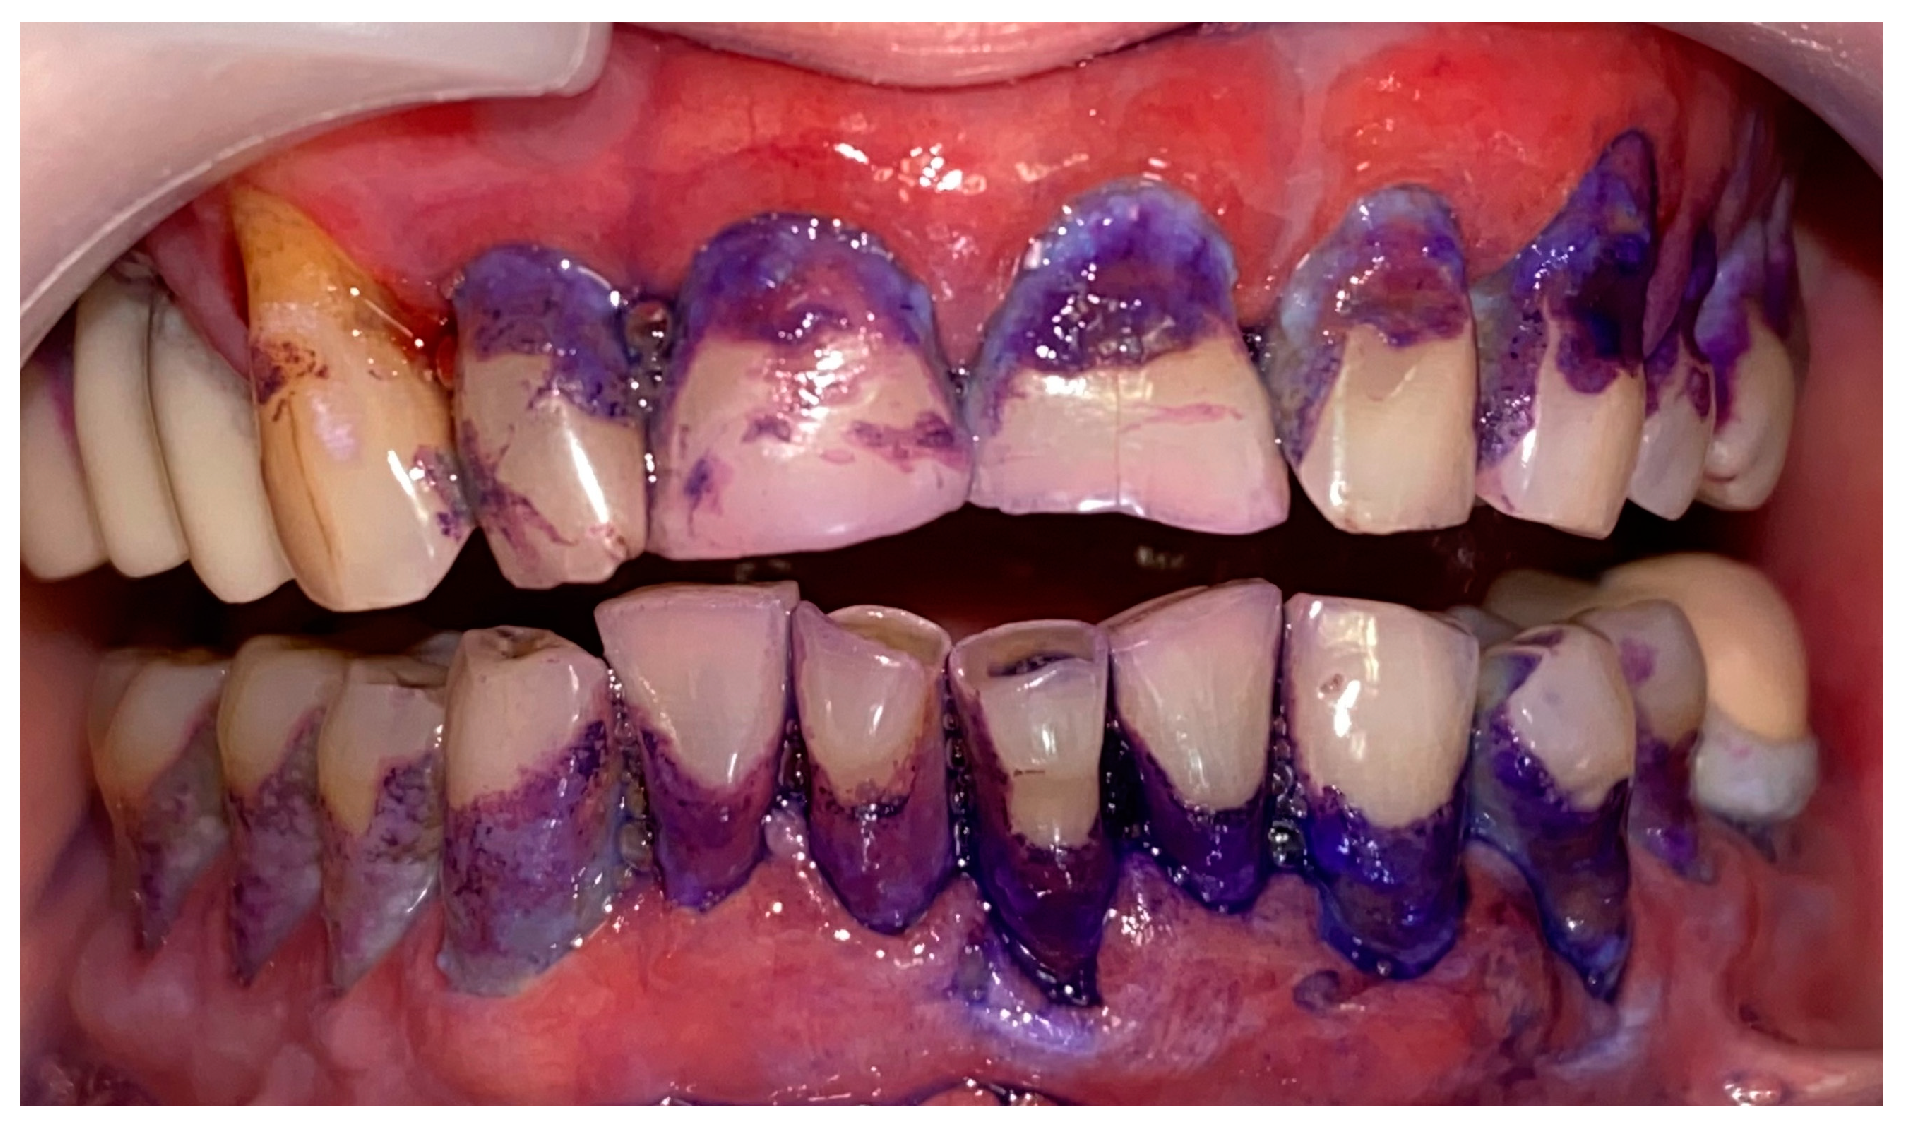

2.1. Clinical Case 1—Mucous Membrane Pemphigoid (MMP)

2.2. Clinical Case 2—Pemphigus Vulgaris (PV)

2.3. Clinical Case 3—Oral Lichen Planus (OLP)